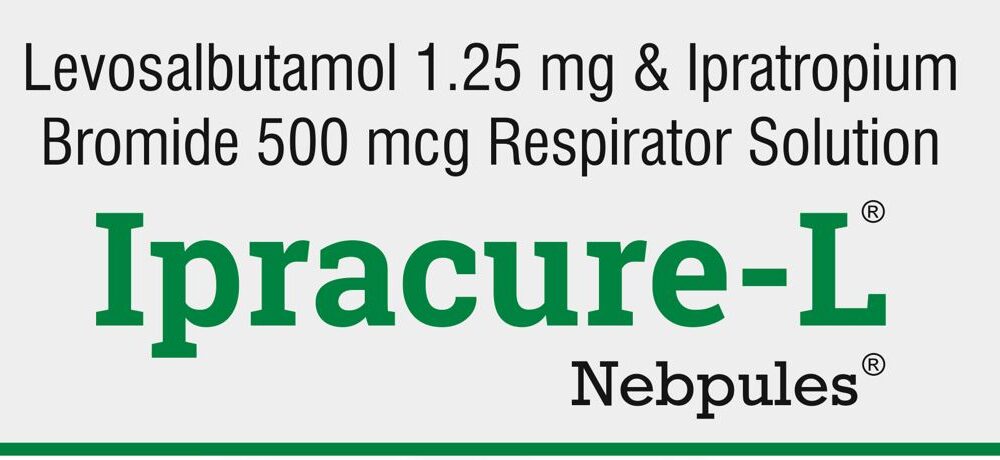

IPRACURE – L NEBPULES (2.5ML Respirator Solution for Nebulizer)

IPRACURE – L Nebpules Levosalbutamol Sulphate + Ipratropium Bromide Prescribing information For the use of a Registered Medical Practitioner or a...